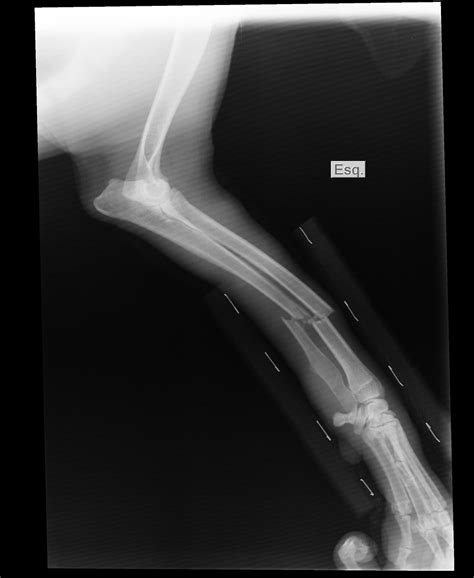

A forearm X-ray is one of the most common diagnostic imaging procedures performed in emergency departments, urgent care centers, and orthopedic clinics. Whether you have suffered a sudden fall, a sports-related injury, or are experiencing unexplained chronic pain, this imaging tool provides doctors with a vital, non-invasive look beneath the skin. By utilizing small amounts of electromagnetic radiation to create images of the bones in the forearm—specifically the radius and the ulna—medical professionals can accurately diagnose fractures, dislocations, and various other structural abnormalities. Understanding the procedure, why it is requested, and what the results mean can help demystify the process and prepare you for your visit to the radiology department.

The primary purpose of a forearm X-ray is to visualize the structural integrity of the bones between the elbow and the wrist. While your doctor may perform a physical examination, physical symptoms alone cannot always distinguish between a severe bruise, a ligament strain, and a bone fracture. An X-ray is the gold standard for ruling out serious injuries.

Injuries to these bones often occur during a "FOOSH"—an acronym for Fall On an Outstretched Hand. When you fall, the impact travels up through the wrist and can easily fracture either or both of these bones. Because they are anatomically linked, a fracture in one often causes structural stress or a corresponding dislocation in the other.

• Fractures: Whether the bone is broken completely, partially (a hairline fracture), or fragmented (comminuted fracture).

• Alignment: Checking if the broken ends of the bone are touching or if they have shifted.

• Dislocations: Ensuring the bones of the elbow and wrist remain properly seated in their joints.